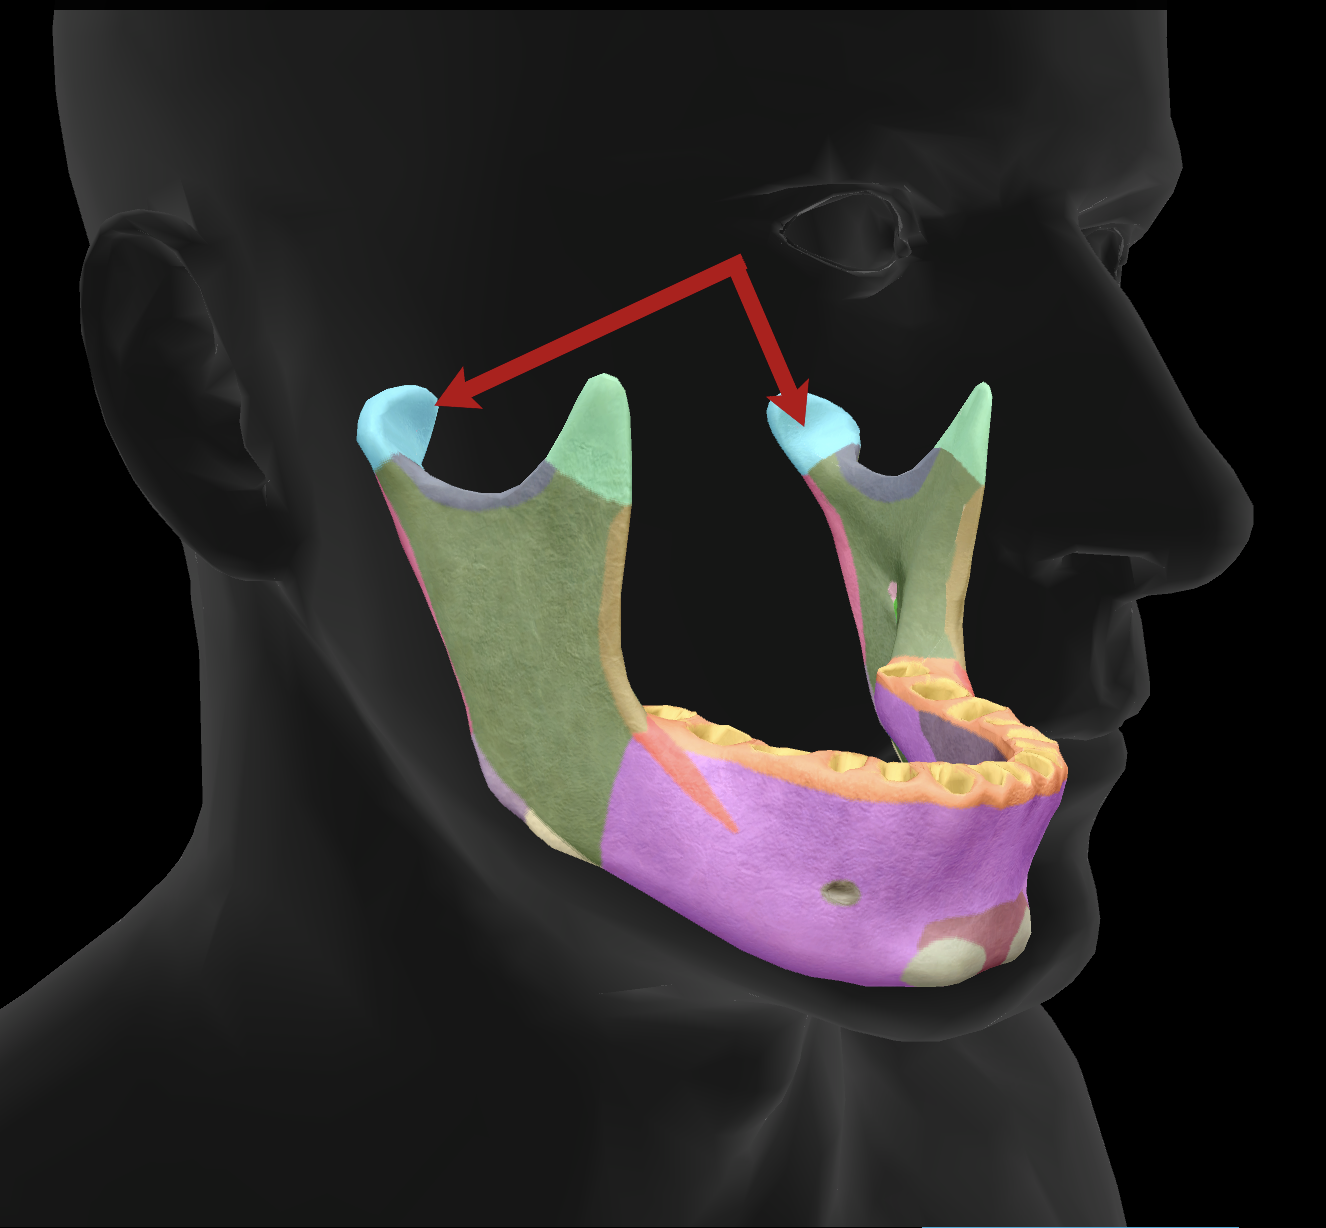

What is the name of this feature?

mandibular condyles

What is the name of this feature?

ramus

What is the name of this feature?

alveolar process

What is the name of this feature?

mandibular notch

What is the name of this feature?

angle

What is the name of this feature?

body

What is the name of this feature?

coronoid process